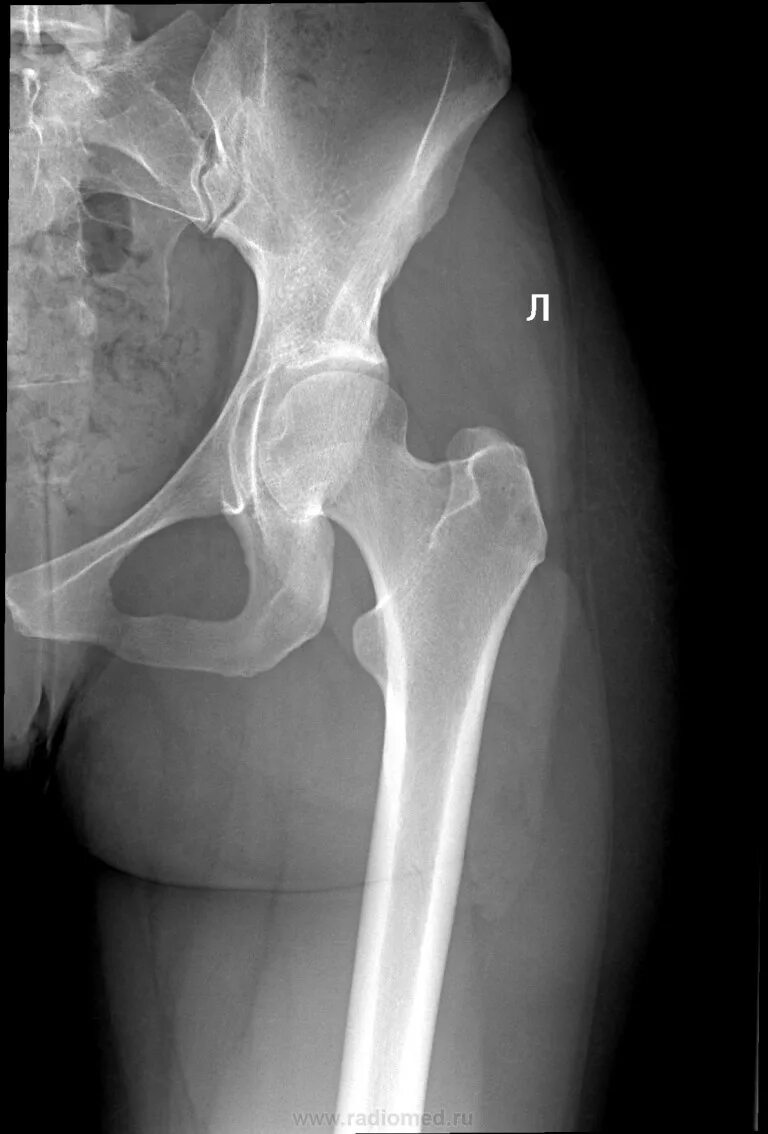

Как лечить коксартроз 1